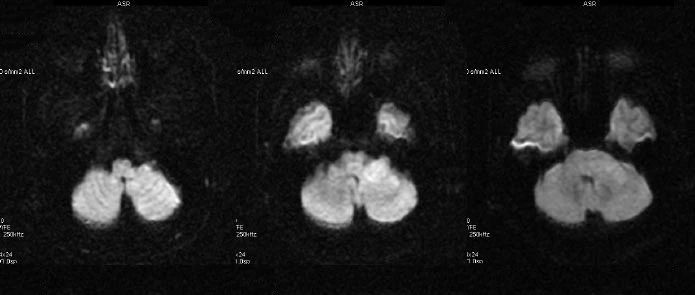

开课啦!江神领衔-神经影像诊断基础训练营(第一期)

01一起探索神经影像如果你是:影像科医师、神内医师、神外医师、急诊科医师、ICU医师、康复医师……那你一定明白:神经影像是放射科、神经(外/内)科、急诊科医生的基本功,精确的影像诊断配合详细的问诊、查体,可以极大程度提升诊断效率和准度。随着相关设备的普及和技术的进步,神经影像在临床诊疗工作中发挥着越来越重要的作用。对于每一位在职业生涯中可能接触到神经影像片子的医生来说,学习影像知识是必要的。你可能想:...